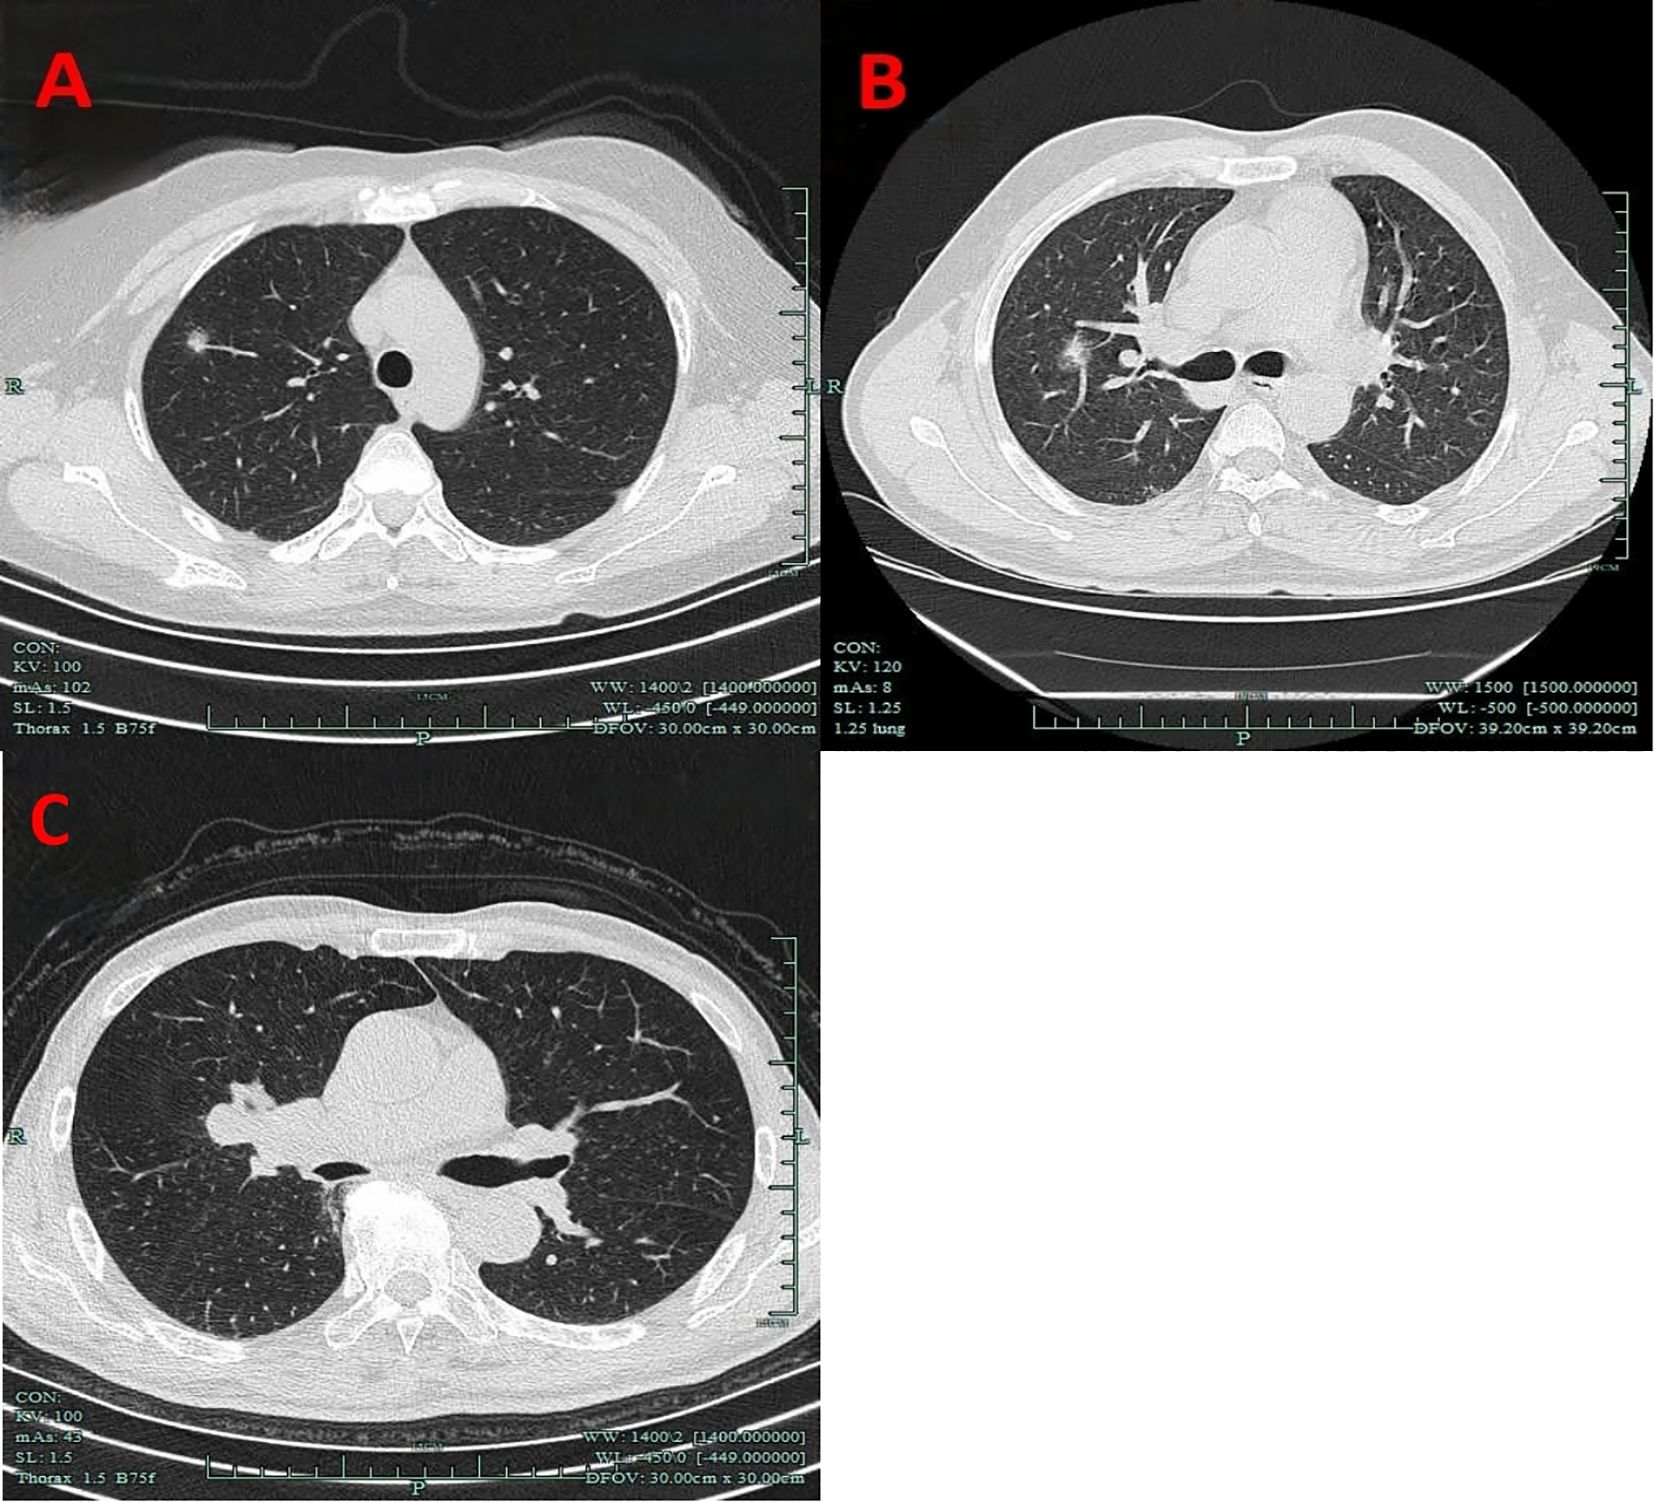

Nodule depth was defined as the distance from the pulmonary nodule to the pleura, relative to the distance from the pleura to the hilum, categorized into the outer one-third and the inner two-thirds, and it did not include centrally located lung masses (Figure 1).

Figure 1. Imaging manifestations of nodule depth. (A) The outer one-third. (B) The inner two-thirds. (C) Centrally located lung masses.

VPC represent a broad concept that includes any form of pleural involvement, such as thickening or adhesion, without penetrating the elastic layer or invading the visceral pleura (14). The key imaging manifestations of VPC include pleural traction, pleural tail sign, pleural attachment, and pleural indentation (Figure 2). In this study, VPC referred exclusively to visceral pleural involvement without visceral pleural invasion (VPI).

Figure 2. Imaging manifestations of VPC. (A) Pleural indentation. (B) Pleural attachment. (C) Pleural traction. (D) Pleural tail sign. VPC, visceral pleural changes.